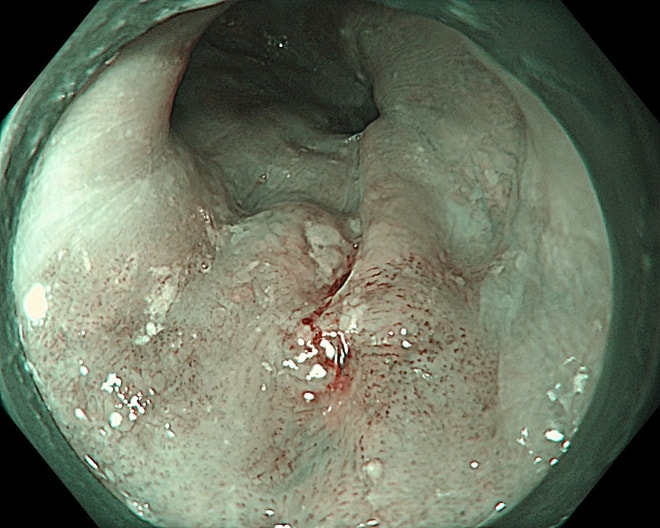

Hình ảnh tổn thương thực quản của bệnh nhân.

Một bệnh nhân 63 tuổi đã được phát hiện ung thư thực quản giai đoạn sớm nhờ công nghệ này và điều trị thành công, xuất viện sau 2 ngày.

Trong một trường hợp khác, bệnh nhân 67 tuổi được phát hiện tổn thương qua nội soi công nghệ cao. Tuy nhiên, qua đánh giá chuyên sâu, bác sĩ xác định tổn thương đã vượt chỉ định điều trị nội soi và chuyển sang phẫu thuật.

Kết quả mô bệnh học sau đó xác nhận ung thư đã xâm lấn dưới niêm mạc, phù hợp với chỉ định ngoại khoa.

Thực tế này cho thấy vai trò quan trọng của nội soi công nghệ cao kết hợp với kinh nghiệm lâm sàng trong việc đánh giá chính xác giai đoạn bệnh, từ đó đưa ra phương pháp điều trị phù hợp, tối ưu.